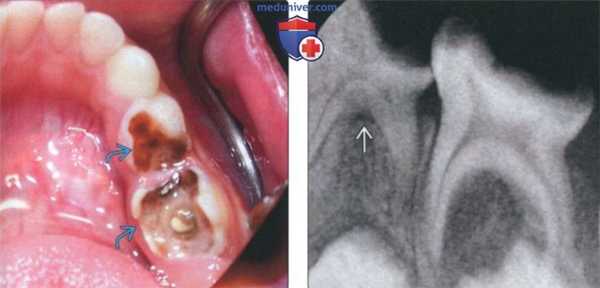

(Слева) На сагиттальной КЛКТ визуализируется крупная радикулярная киста, смещающая дно верхнечелюстной пазухи кверху и занимающая ее нижнюю треть. Обратите внимание на воспалительные изменения пазухи.

(Справа) На профильном срезе (КЛКТ) визуализируется крупная кариозная полостьв нежизнеспособном моляре; также видны два периапикальных абсцесса. Поражение щечного корня приводит к деструкции щечной кортикальной пластинки альвеолярного отростка. Сужение пульповых каналов необходимо отметить как вероятное осложнение эндодонтическою лечения.

(Слева) На фотографии виден глубокий кариес первого и второго временных моляров.

(Справа) На периапикальной рентгенограмме у этого же пациента определяется расширение области фуркации «мертвого» временного моляра. Рарефицирующий остеит временных моляров возникает в области фуркации вследствие минимального расстояния между пульповой камерой и костной тканью возле фуркации.